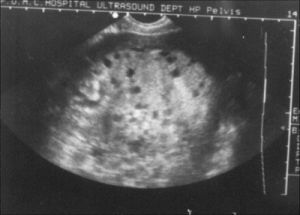

8.疑有肝、腎轉移者,如有肝區痛,肝脾腫大,黃疸等及腎腫大,血尿等應行肝、腎B超及CT檢查。